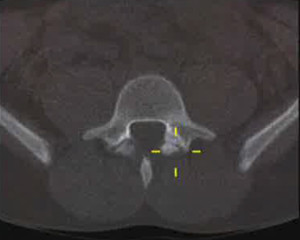

La gran mayoría de los defectos espondilóticos ocurren en el nivel L5 (85 – 95%), siendo L4 el segundo nivel más comúnmente involucrado (5-15%), mientras que las zonas lumbares superiores rara vez se ven afectadas. Este defecto se ve con relativa frecuencia en los estudios radiográficos con vistas posteroanterior y lateral, aunque las vistas dinámicas y oblicuas parecen determinar la estabilidad vertebral y conducir al diagnóstico.

Desafortunadamente, se realizan diagnósticos erróneos de espondilólisis. Un factor de complicación en las primeras etapas de la enfermedad que conduce a un diagnóstico erróneo es el hecho de que las radiografías simples, incluso las oblicuas, pueden no ser útiles en la etapa de fractura por sobrecarga. Otras técnicas de imagen, como la gammagrafía ósea, posiblemente, la resonancia magnética o Tomografía computarizada de emisión monofotónica (SPECT) deben ser utilizadas al inicio del proceso de diagnóstico. En el ámbito de la atención primaria, el diagnóstico precoz de elemento de participación posterior relacionado con el dolor lumbar, ya sea en la etapa de la fractura por sobrecarga del pars o por espondilolisis temprana, puede prevenir la progresión de la enfermedad y evitar la necesidad de una intervención quirúrgica.